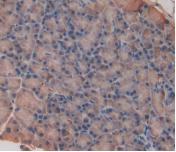

DAB staining on IHC-P; Samples: Rat Liver Tissue; Primary Ab: 30µg/ml Mouse Anti-Rat IL33 Antibody Figure. DAB staining on IHC-P;

Samples: Rat Stomach Tissue. Figure. DAB staining on IHC-P;Samples: Rat Pancreas Tissue.